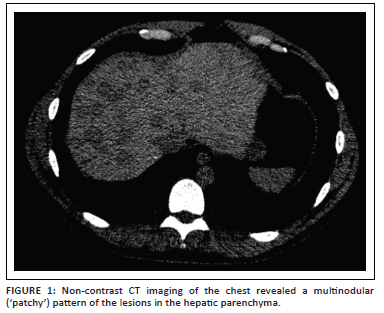

Chest CT was performed independently at another clinic. A CD archive of the CT scan without contrast enhancement was provided for a second-opinion. CT analysis demonstrated no pathological changes in the lung parenchyma. At the lower margin of the field of view, a heterogeneous liver parenchyma was noted with numerous variable-sized hypodense nodular foci of round or oval shape in an unequal distribution. The maximum diameter was 2.5 cm. Density reading of these liver lesions was about +30 HU (absolute low attenuation), with background liver parenchyma density measuring +50 HU. Furthermore, there was no associated mass effect. Vascular structures (hepatic veins and portal branches) traversed the nodules without disruption (Figure 1). The obvious etiological identity of the lesions was not determined. In accordance with the data from the CT scans, elastography for assessment of the degree of liver fibrosis, MRI with contrast for further characterisation of the nodules and evaluation of the laboratory profile was planned.